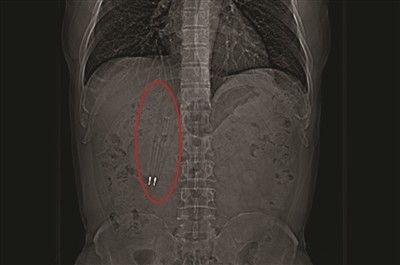

CT中能清晰看到亮闪闪的笔尖。

王先生吞下去的这两支笔都是塑料的,从CT上看,还可以看到笔里的金属弹簧和金属笔尖在闪闪发光。